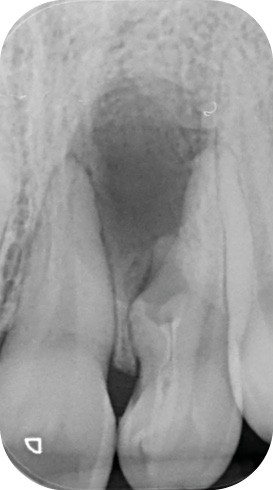

L’examen rétro-alvéolaire montre une anatomie atypique évoquant une invagination de l’émail communiquant avec le parodonte profond (dens invaginatus type III a selon Oehlers) [2] (fig. 1). L’analyse CBCT permet de mieux visualiser l’étendue de la lésion et l’anatomie radiculaire de la 22. L’invagination et le canal ont deux trajets indépendants sur toute leur longueur (fig. 2 et fig. 3a et b).